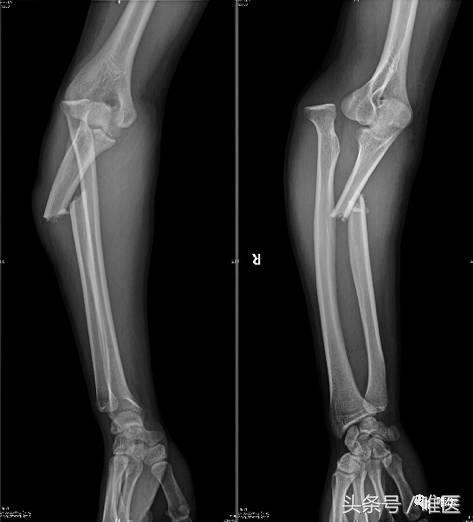

男性,19岁,自行车摔伤,右其前臂孟氏骨折。

▣ X线